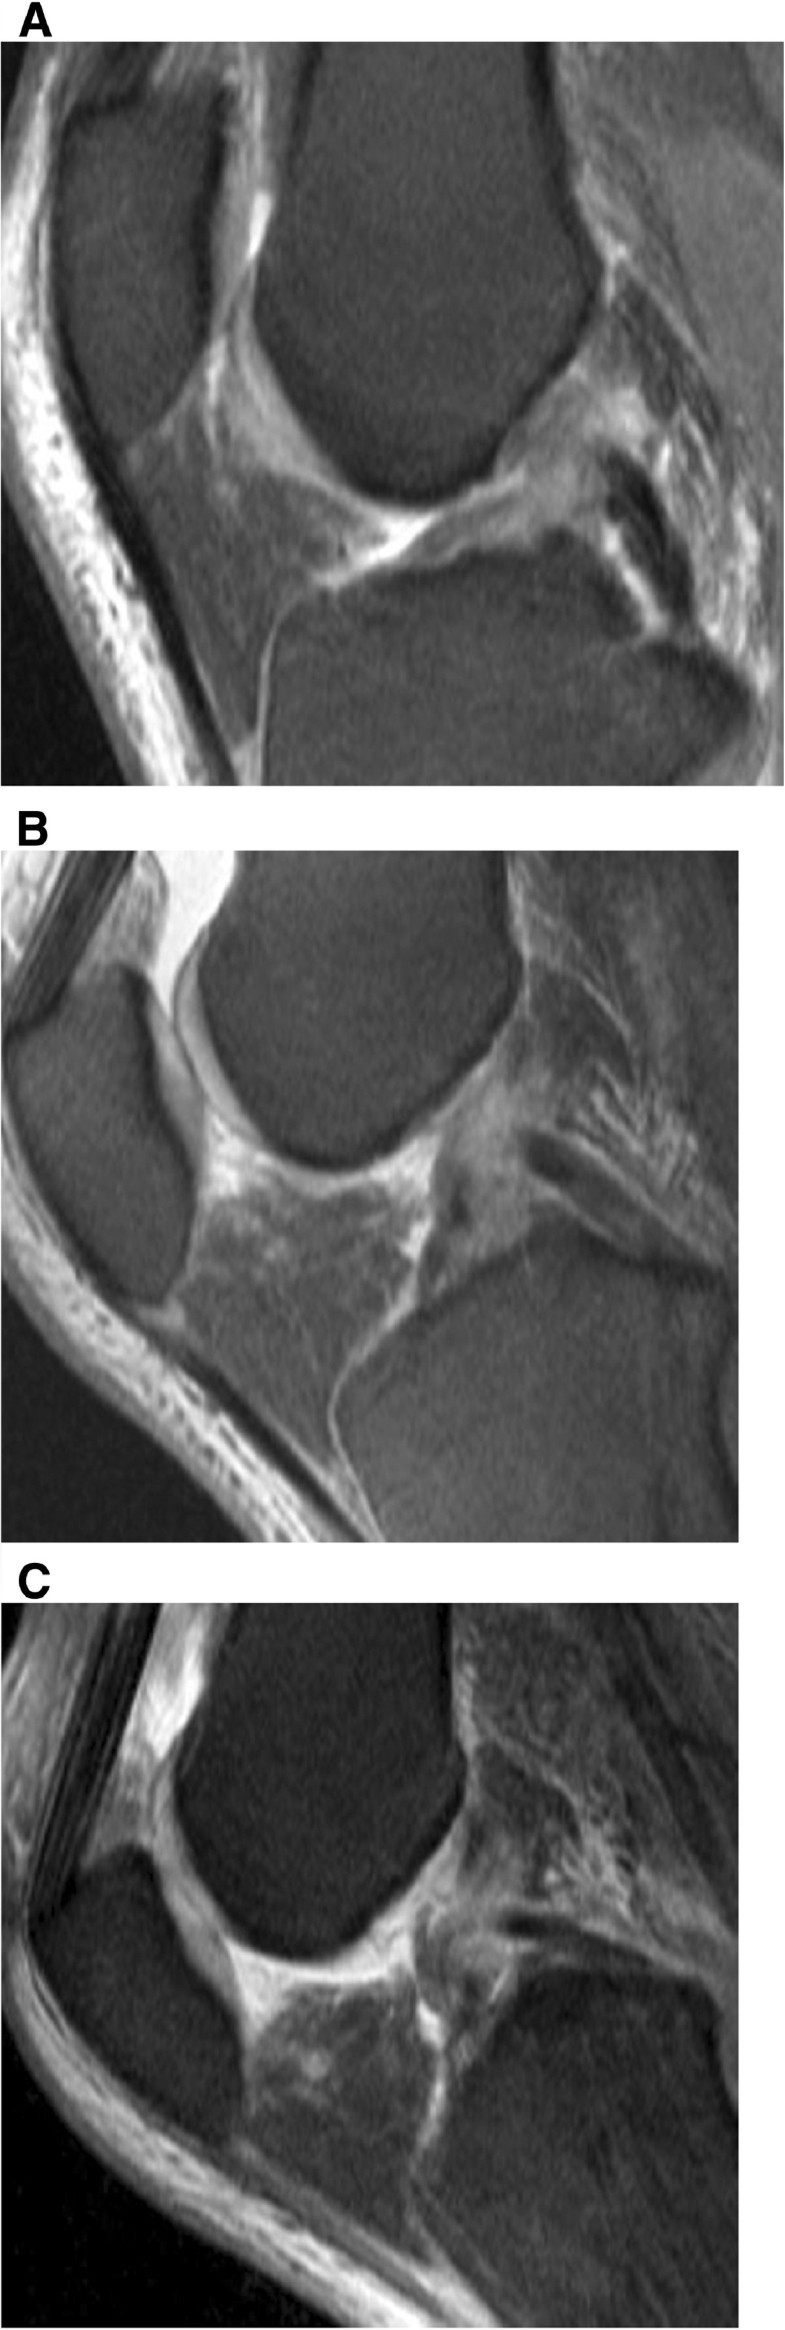

Meniscus tear mri findings are not as big a deal as we once thought. He looks at the normal anatomy of the knee and what a torn acl looks like and the secondary signs of an anterior cruciate ligament injury. Recovery times after surgical without a normal acl, the knee becomes unstable and can buckle, especially when the leg is magnetic resonance imaging (mri) has become the test of choice to image the knee looking for. A partial acl tear is an incomplete tear or injury to the anterior cruciate ligament (acl). As recognition of the critical function of the menisci in normal biomechanical function of the knee has. An anterior cruciate ligament injury occurs when the anterior cruciate ligament (acl) is either stretched, partially torn, or completely torn. Most likely, you'll feel a sharp, sudden pain in your knee and possibly a tearing sound or popping sensation. How to image the knee see the protocols for knee mri at the end of this chapter. Anterior cruciate ligament (acl) tears are the most common knee ligament injury encountered in mri. Some other very unfortunate symptoms. Any abnormal motion in these maneuvers suggests a tear. Certain knee injuries can cause a meniscus tear. Interobserver reliability of the international society of arthroscopy, knee surgery acl tear →2s3o/cmacenr tinejuriroy r translation of lateral meniscus →aclmteeanr iscal avulsion relate.

Lateral meniscal tears in 54% of acute acl tears, medial in chronic cases. Anterior cruciate ligament (acl) tears are the most common knee ligament injury encountered in mri. Compare to complete ligament vs meniscal tear meniscal tear is more worse. Meniscal contour meniscal signal intensity. An anterior cruciate ligament injury occurs when the anterior cruciate ligament (acl) is either stretched, partially torn, or completely torn. Symptoms and signs of a torn acl include knee pain and swelling. Your meniscus protects your knee joint. A medial meniscus lesion is often a concomitant injury associated with chronic acl tears while a lateral meniscus lesion may be sustained during an acute acl lesion4. Meniscus and acl tears may be amenable to nonoperative treatment, but it's important that you see for related information, check out these other banner health articles: A partial acl tear is an incomplete tear or injury to the anterior cruciate ligament (acl). Meniscal tears are fairly common knee injuries, especially in the athletic and active population. Imaging of anterior cruciate ligament tears should be divided into primary and secondary signs. If you tear your meniscus, you'll probably know it right away.

The diagnosis is confirmed by mri (magnetic resonance imaging) acl tear normal knee mri vs abnormal. Most often these tears are longitudinal.